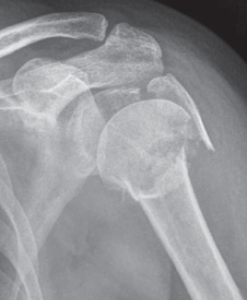

Der klassische Verschleiß des Schultergelenkes tritt im Vergleich zum Hüft- und Kniegelenk beim älteren Menschen seltener auf. Hierbei erfolgen eine Zerstörung des Gelenkknorpels und die Deformierung der Gelenkflächen, die zu einer schmerzhaften Bewegungseinschränkung des Schultergelenkes führen (Abb. 34, 37).

Oberarmkopfnekrose